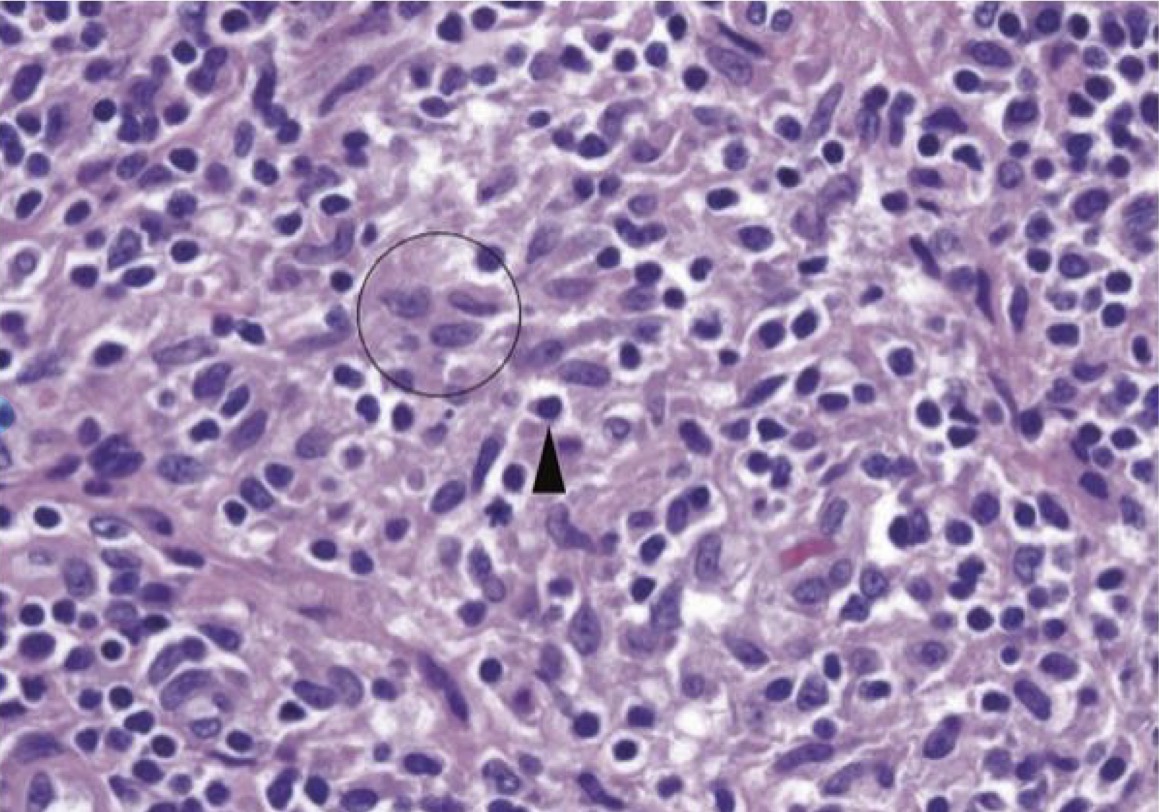

A- identify

B- identify the circle with describe

C- identify the arrowhead with describe

A- Chronic inflammation ( histocyte and lymphocyte in inflammatory tissue )

B- ( circle ) Histocyte , Pale folded nuclei surrounded by light pink cytoplasm ,The cell borders are indistinct , pale chromatin

C- ( arrowhead ) Lymphocyte , darker chromatin